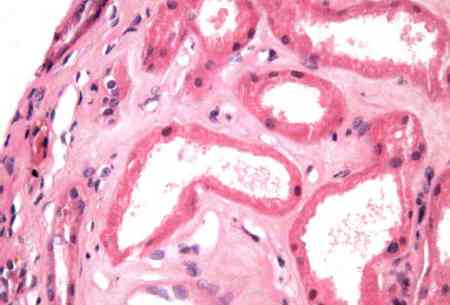

- биопсия почки